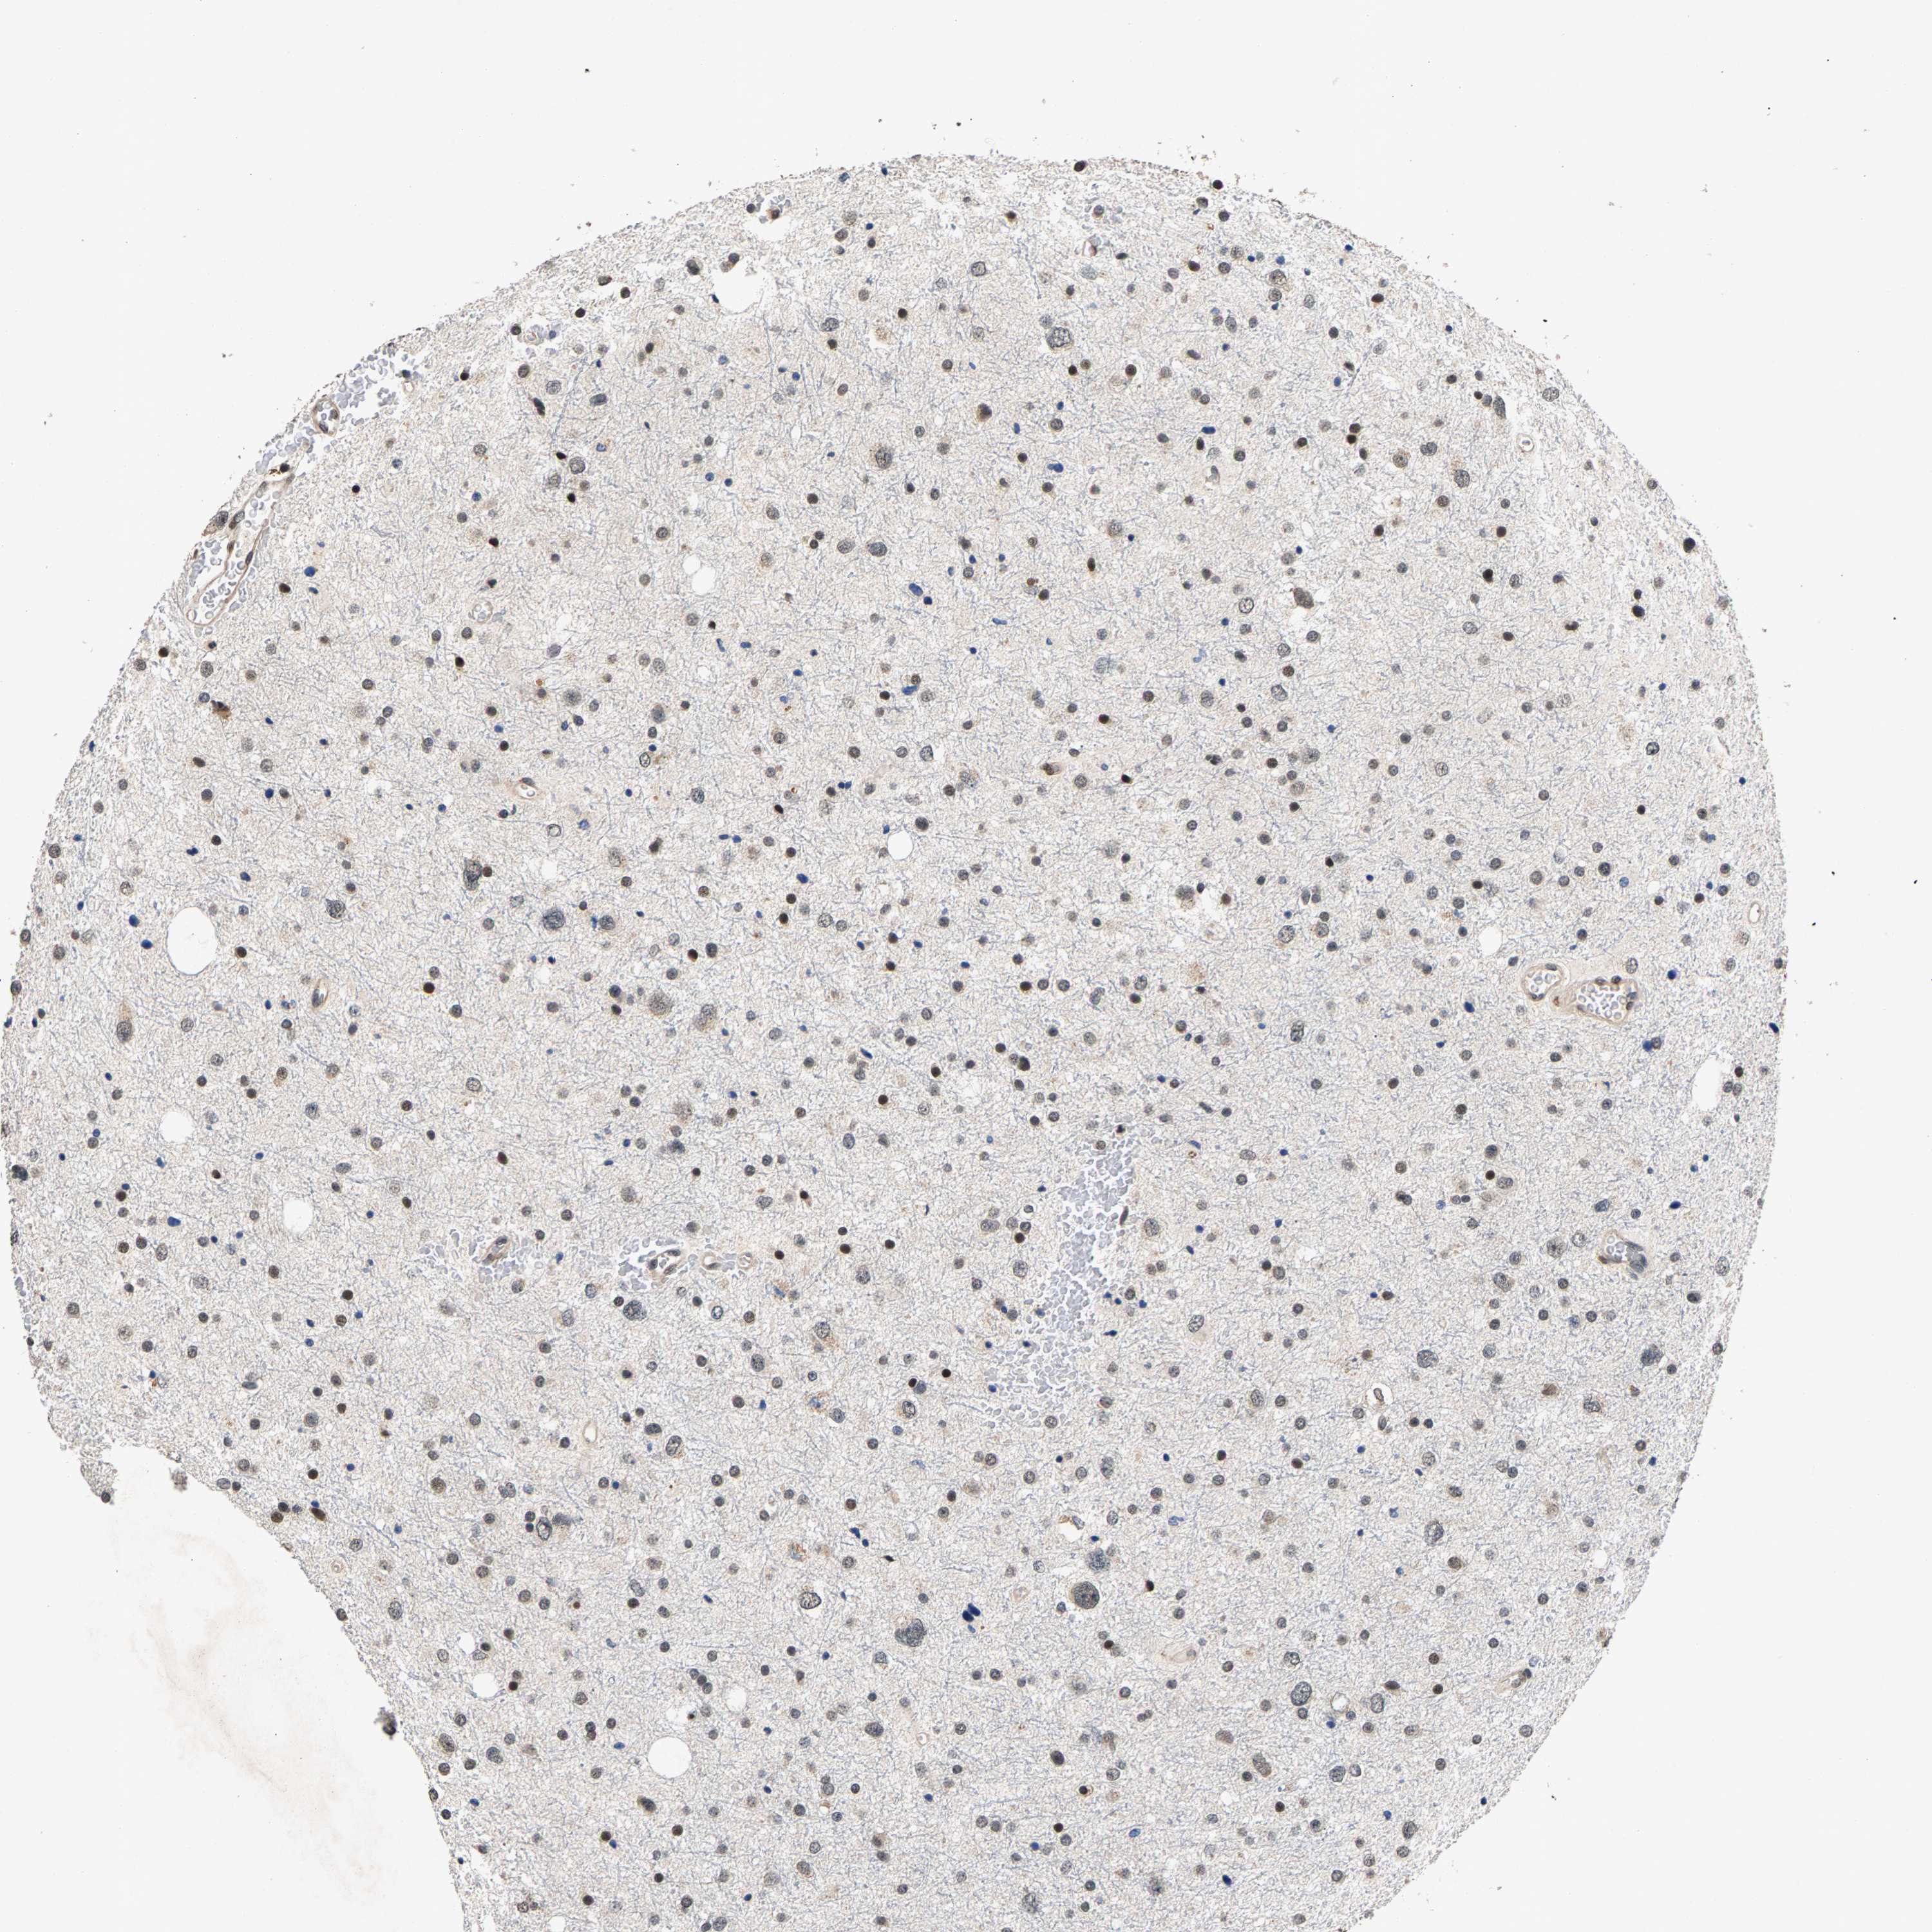

GLIOMA - Protein expressioni

A mouse-over function shows sample information and annotation data. Click on an image to view it in a full screen mode. Samples can be filtered based on level of antibody staining by selecting one or several of the following categories: high, medium, low and not detected. The assay and annotation is described here.

Note that samples used for immunohistochemistry by the Human Protein Atlas do not correspond to samples in the TCGA dataset.

Antibody stainingi

Antibody staining in the annotated cell types in the current human tissue is reported as not detected, low, medium, or high, based on conventional immunohistochemistry profiling in selected tissues. This score is based on the combination of the staining intensity and fraction of stained cells.

Each image is clickable and will lead to virtual microscopy that enables deeper exploration of all samples and also displays staining intensity scores, fraction scores and subcellular localization as well as patient and tissue information for each sample.

Antibody HPA019232

Antibody HPA021497

Antibody HPA021768

Staining

High

Medium

Low

Not detected

Intensity

Strong

Moderate

Weak

Negative

Quantity

>75%

75%-25%

<25%

None

Location

Nuclear

Cytoplasmic/membranous

Cytoplasmic/membranous,nuclear

Glioma, malignant, High grade

Glioma, malignant, Low grade